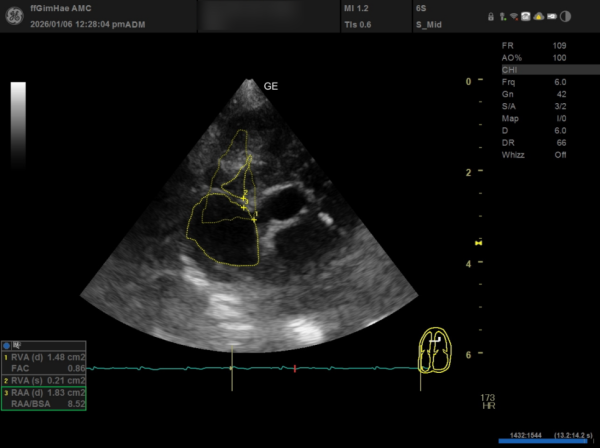

④ RA(우심방) 확장

RAA/BSA: 8.52로 우심방의 유의미한 확장이 확인되었습니다.